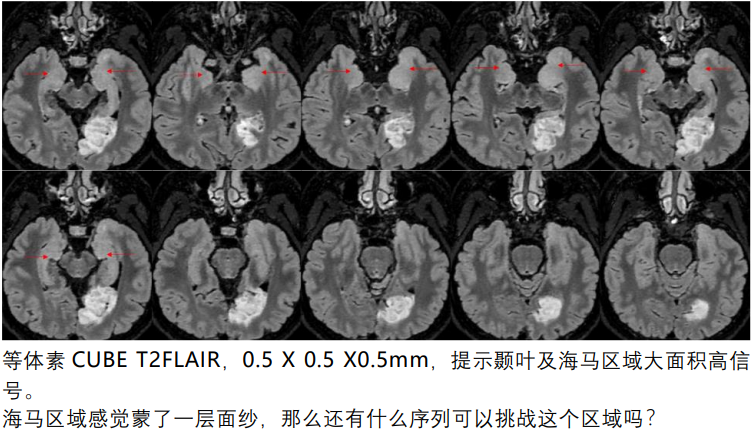

颞叶及海马区域显著高信号。这应该才是导致癫痫频繁发作的真正原因。